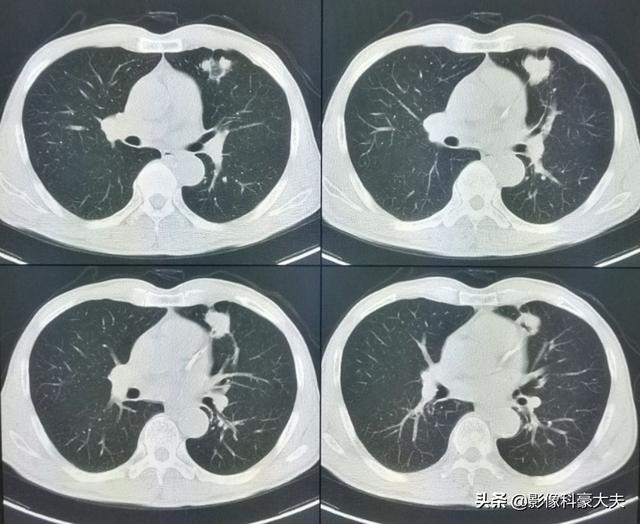

左肺にあるこの不規則な結節が原発巣で、わずか2.6cmしかない。このような骨転移を伴う肺がんは、もはや手術不可能です。肺がんはあまりにもありふれた病気であり、初期症状の中には非典型的なものや無症状のものさえあるからだ。肺がんの約30%では、転移の症状が最初の症状であり、さらなる肺がんが発見される前に転移が最初に発見される。

幸いこの患者は治療に敏感で、化学療法と標的療法に基づく治療を組み合わせて5年間治療を受けてきた。

直近のCT検査の結果、原発巣はかなり縮小しており、5年以上保菌したまま生きられたのは幸運だった!